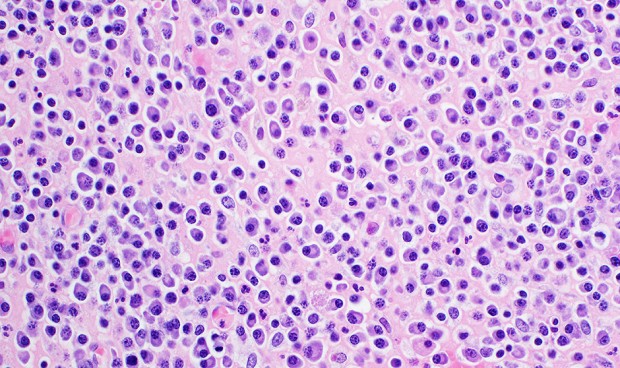

Un estudio descubre un nuevo mecanismo que 'asesina' de forma programada las células del

mieloma múltiple. El bloqueo de la secretasa 61 (

Sec61) por

micolactona induce muerte celular selectiva en este tipo de cáncer. Los hallazgos identifican a Sec61 como una vulnerabilidad terapéutica en el mieloma múltiple y, potencialmente, en todos los demás tipos de cáncer que necesitan un translocón Sec61 activo para sobrevivir.